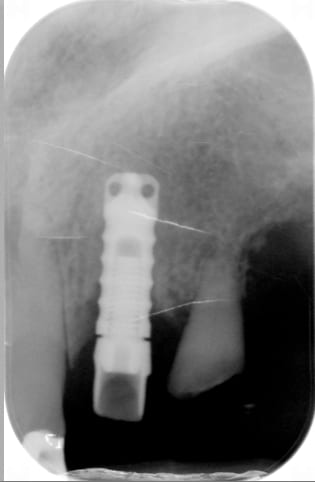

Implant posé il y a trente ans à l'hôpital de dijon. J'ai fait une recherche sur whatisimpant qui n'a rien donné. Une idée ?

TBR....100% sûr

https://whatimplantisthat.com/implants/details/periosave-classic-ocatagon

TBR lisse, pour info le pas de vis est le même que les anthofit d'Anthogyr je crois